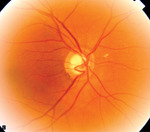

Rycina 1B. Grubość włókien nerwowych nerwu wzrokowego z ryciny 1A reprezentuje czarna pofalowana linia

Zdrowy człowiek posiada niewielkie zagłębienie w środku tarczy nerwu wzrokowego (wnęka naczyniowa) pozwalające dostać się żyle i tętnicy środkowej siatkówki do oka. Stosunek średnicy tarczy nerwu wzrokowego do zagłębienia, oznaczany skrótem c/d (cup – zagłębienie/disc – tarcza nerwu wzrokowego), wynosi najczęściej 0,3-0,4 (ryc. 1A-B). Utrata włókien nerwowych powoduje poszerzanie się zagłębienia nerwu wzrokowego (ryc. 2A-C) aż do momentu, gdy średnica tarczy jest prawie równa średnicy zagłębienia (c/d = 0,9) – mówimy wtedy o jaskrze prawie dokonanej. W tym przypadku ostrość wzroku określa się jako poczucie światła, z reguły po stronie skroniowej chorego oka. Jaskra dokonana oznacza natomiast całkowitą utratę widzenia, czyli brak poczucia światła.